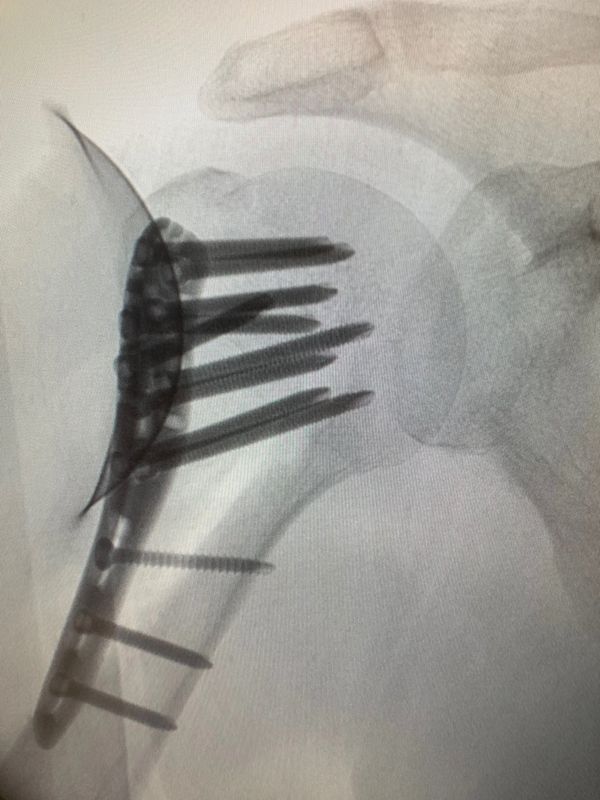

Dr ufuk nalbantoğlu. Percutaneous cannulated screw fixation in the treatment of distal radius fractures. özkan ufuk nalbantoğlu has international and national patents. Ufuk nalbantoğlu okan tok. Okan tok 90 530 246 56 75 90 535 412 12 05.

Ufuk nalbantoğlu orthopedics and traumatology at acibadem university atakent hospital speciality orthopedics. Dr öğr üyesi özkan ufuk nalbantoğlu. Arch orthop trauma surgery 2012. Gündoğan k aslan e.